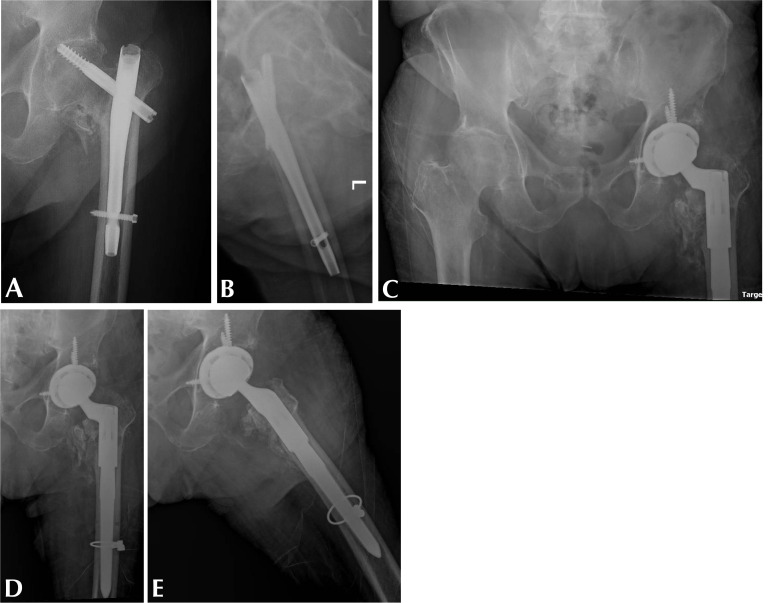

Abstract Image